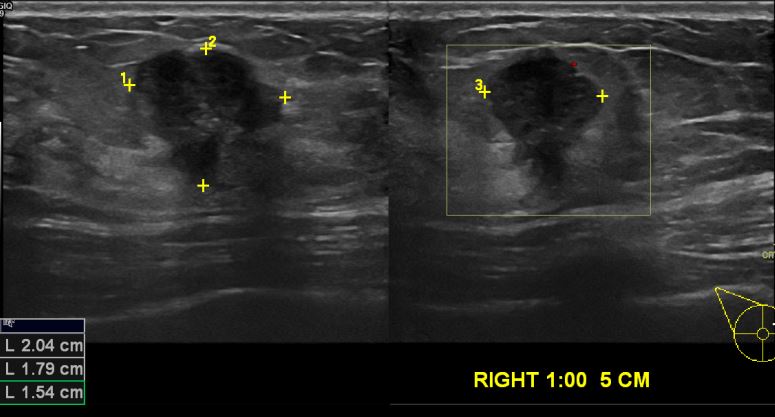

2 달전에 우측유방 멍울발견하여 정밀검진위해 내원하신43세 여자환자 분으로

우측유방  1시방향으로 중심핵검사 실시하여 침윤성유관암 진단되셨습니다.